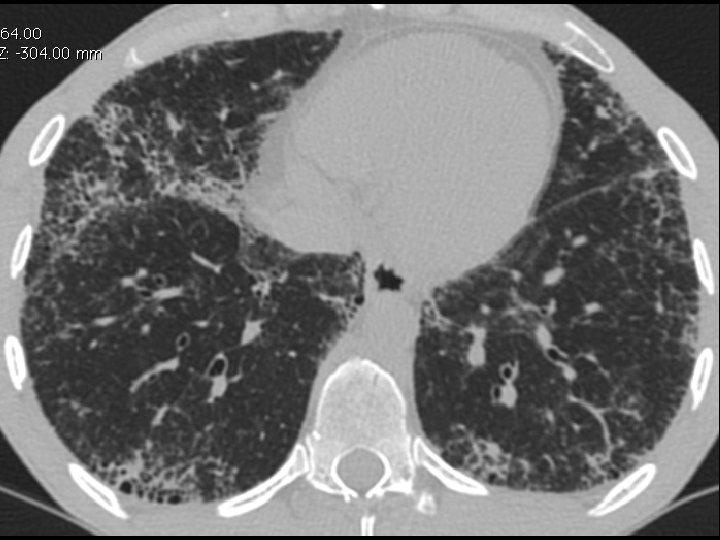

High-resolution CT scan

Subpleural, basal predominance Reticular abnormality Honeycombing with traction bronchiectasis UIPUIP Pattern

Subpleural, basal predominance Reticular abnormality Honeycombing with traction bronchiectasis Profuse micronodules UIPUIP Pattern Inconsistent with UIP Pattern

39 yo caucasian male, works in car collision repair and painting Multiple allergies, Gastroesophageal reflux disease and Thrombocytopenia of unknown etiology Smoker. No drugs CT: Reticular abnormality and honeycombing of subpleural basal predominance + micronodules Lung function tests: decreased diffusion capacity of the lung Blood tests: small increase of ESR and CRP; Autoimmune screening blood tests were normal BAL: normal celularity, with a mild increase in the neutrophil and eosinophil count

39 yo caucasian male, works in car collision repair and painting Multiple allergies, Gastroesophageal reflux disease and Thrombocytopenia of unknown etiology Smoker. No drugs CT: Reticular abnormality and honeycombing of subpleural basal predominance + micronodules Lung function tests: decreased diffusion capacity of the lung Blood tests: small increase of ESR and CRP; Autoimmune Screening Blood Tests were normal BAL: normal celularity, with a mild increase in the neutrophil and eosinophil count Definitive diagnosis can be established? Additional diagnostic tests required? Which tests?